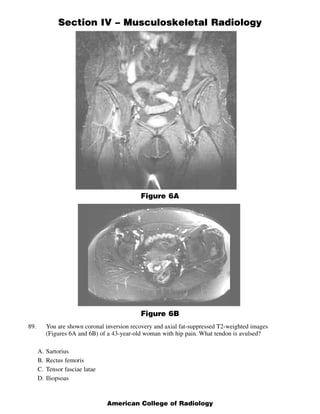

This document contains a radiology case study with 4 images (Figures 1-4) and accompanying questions. Figure 1 shows a lateral cervical spine x-ray. The diagnosis is ankylosing spondylitis based on diffuse bony ankylosis throughout the cervical spine. Figure 2 shows MRI images of the knee with a diagnosis of discoid meniscus due to excessive meniscal tissue. Figure 3 shows x-rays of the leg with a diagnosis of Brodie's abscess, seen as an elongated lytic lesion in the tibia. Figure 4 shows knee images of a 13-year-old boy with a diagnosis of chondroblastoma, seen as a well-defined lesion in the proximal tib